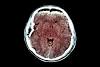

Neurosurgons propose a new framework for assessing traumatic brain injuries Each year in the United States, nearly 5 million adults and children seek medical care for a traumatic brain injury. Now after more than half a century, based on a mountain of data, and a team of international experts, a new proposal published in ...

A New System Aims to Save Injured Brains and Lives Dr. Geoffrey Manley, a neurosurgeon at the University of California, San Francisco, wants the medical establishment to change the way it deals with brain injuries. His work is motivated in part by what happened to a police officer he treated in 2002, ...

UVA Innovation Offers Hope for Safer Brain Lesion Treatment A new, incision-free technique developed at UVA Health shows strong early results in treating cerebral cavernous malformations, nearly halting lesion growth. Cavernous malformations, or cavernomas, are clusters of enlarged blood vessels that can form ...